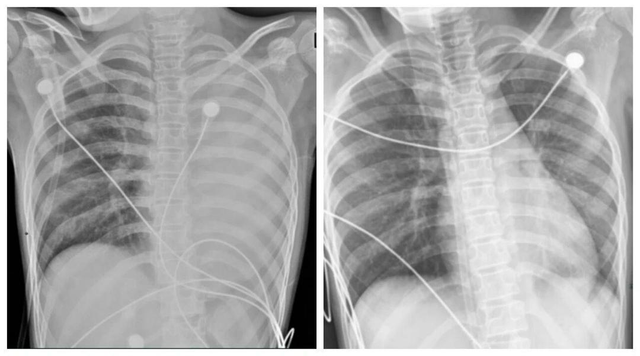

Bé trai 3 tuổi t:ử vo:ng chỉ sau 1 ngày mắc cúm A, bác sĩ cảnh báo có dấu hiệu này cần đi khám ngay

Bé trai đột ngột sốt cao kèm chân tay lạnh vào rạng sáng 10/11. Khi đưa đi cấp cứu, bé đã sốt tới 39,8 độ C và đưRead More…